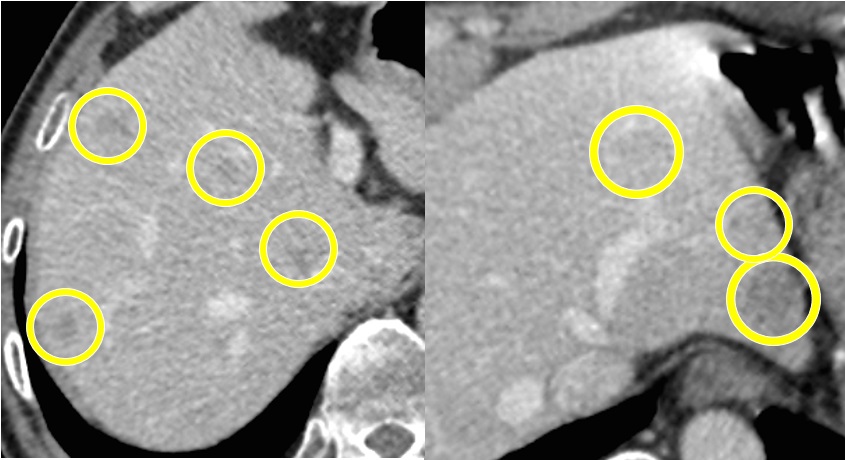

図2. 転移性肝がん|肝臓の病気

上図も転移性肝がんの手術前のCTですが、黄色の丸で囲ってある部位に腫瘍が存在します。この症例では肝臓の左右に腫瘍が多発していました。